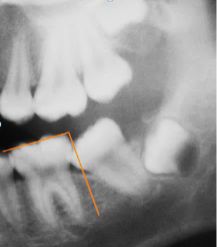

A cross-sectional study was conducted using non-probability, consecutive sampling from a universe of 4,500 records of initial consultations in two private clinics in the city of Temuco, Chile. The records of 2095 individuals of both sexes were analyzed. Criteria for inclusion: clinical records with printed panoramic radiographies taken between 2008 and 2013 to children aged between 7 and 13, with at least one second permanent molar with mesial contact point located under the amelocemental junction of the first permanent molar. Criteria for exclusion: presence of syndromic pathology and second permanent molar absent or divergent (distal coronal inclination). The sample was formed by 370 clinical records that fulfilled the criteria for inclusion. Finally, 740 permanent lower second molars were analyzed. The variables measured were angle of second molar (Fig.1), angle of first and second permanent lower molars in relation to occlusal plane (Fig. 2), invasion of distal space of first molar by second molar (Fig. 3), distance between distal edge of first molar and front edge of ramus (Fig. 4).

We also measured the distance between the mesial contact point of the second molar and the amelocemental junction of the first permanent molar. To measure the angle of the second molar two lines were drawn: one in the center of the axis of the first molar and the other in the second molar. To preserve objectivity in the lines, three midpoints were determined in both molars: coronal, cervical and apical (Fig.1).

Fig. 1. Angle of inclination between 1st and 2nd lower permanent molar